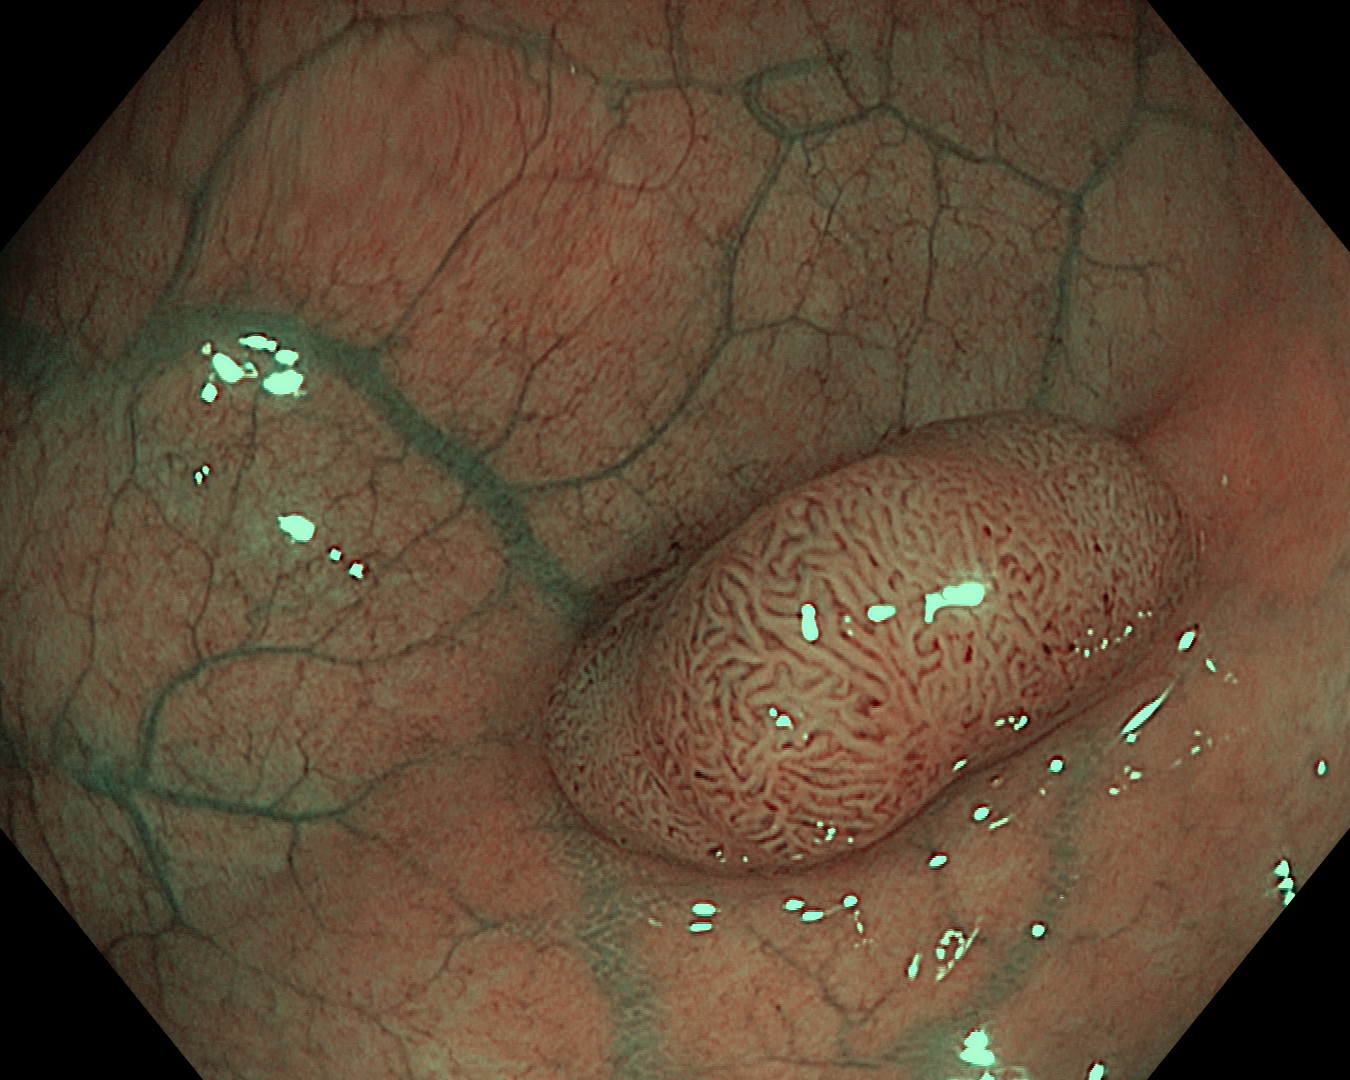

Bitno je napomenuti da su ove napredne slikovne metode (digitalno uvećanje slike i prikaz pod uskopojasnim spektrom), naročito korisne u endoskopskoj analizi polipa kolona. Ovdje u većini slučajeva nije potrebna dodatna patohistološka analiza, čime se ubrzava postupak dijagnostike, uz financijske uštede sa strane pacijenta

Prikaz polipa kolona pod normalnim svjetlom | Prikaz polipa kolona u uskopojasnom spektru |

Prikaz polipa kolona u uskopojasnom spektru s uvećanjem